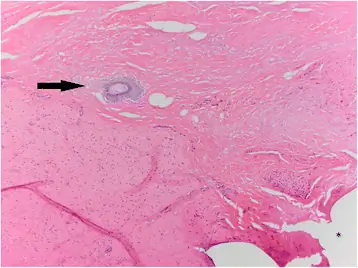

Животное 2 было помещено в закрытую больницу CNPRC с неспецифической травмой, связанной с укушенными ранами и рваными ранами правой ноги, левой щеки и шеи, через 1 день после возвращения в домашнюю клетку, то есть через 7 дней после размещения Васалгеля. При осмотре выявлено сильное опухание, ощутимое в левом месте операции, распространяющееся в мошонку. Невозможно определить, была ли опухоль связана с травмой в результате драки с другими мужчинами, гранулемы спермы или гидроцеле. Хотя во время физического осмотра не было обнаружено никаких внешних признаков травмы области половых органов, нельзя исключать возможную внутреннюю травму от агрессии между мужчинами. Была выбрана исследовательская операция, в результате которой была предпринята попытка выполнить традиционную вазэктомию, как описано выше (с использованием 4-0 проленов), из-за наличия гидроцеле. Предполагаемый семявыносящий проток был представлен для гистопатологии. Гистопатология показала, что в семенном канатике было несколько областей пиогранулематозного воспаления с примесью свободных сперматид, фибрина и кровоизлияний вдоль поверхности семенного канатика, что подтверждает наличие левой сперматозоидной гранулемы (рис. 1). Смежные с этими областями, но не связанные с каким-либо воспалением, были небольшими нерегулярными очагами от базофильного до амфофильного от зернистого до кристаллического материала, предположительно являющегося Васалгелем (рис. 2). Таким образом, оказалось, что воспаление было связано с наличием внепросветной спермы, а не с наличием Vasalgel. Изучив гистопатологическое и медицинское заключение, было установлено, что присутствие Васалгеля было случайным послеоперационным осложнением.

Животное 2: тот же разрез, что и на рис. 1. В центре изображения находится небольшая нерегулярная глобула от базофильного до амфофильного материала (черная стрелка, предположительно Vasalgel). Там нет никакого связанного воспаления. Отмечены четкие участки швов (звездочка). H & E, 100x

Изображение в полном размере